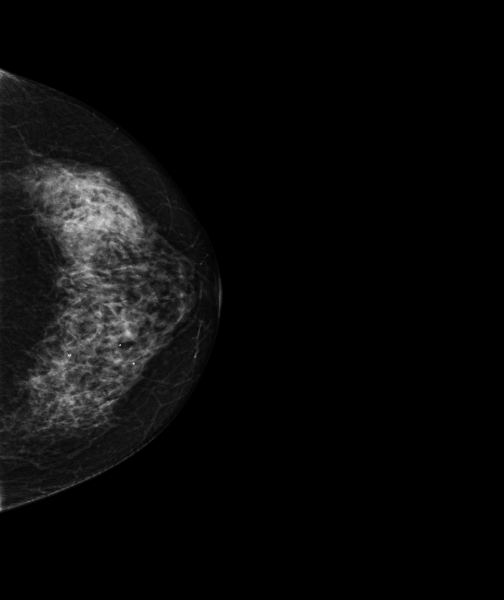

Case of the week (week 30, 2023)

69-year-old female patient, coming in for a breast cancer screening exam.

MammoScreen indicates an external right breast lesion with architectural distortion.

The biopsy performed indicates an infiltrating ductal carcinoma SBR 1, RH+, HER2-, with 5% proliferative activity. With its scoring of 5, MammoScreen successfully alerted the radiologist and facilitated the detection of the carcinoma.